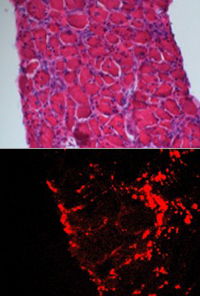

| FASEB Journal Shown is a diaphragm muscle of a mouse with muscular dystrophy (top). Pictured below are fluorescent nanoparticles (red) lodged in the diaphragm. |

When injected into the bloodstream, according to Wickline, the nanoparticles accumulate in areas of inflammation, where damaged tissues have leaky blood vessels and are undergoing cell death and repair.

"The nanoparticles tend to penetrate and be retained in areas of inflammation," Wickline said. "Then they release the rapamycin over a period of time, so the drug itself can permeate the muscle tissue."